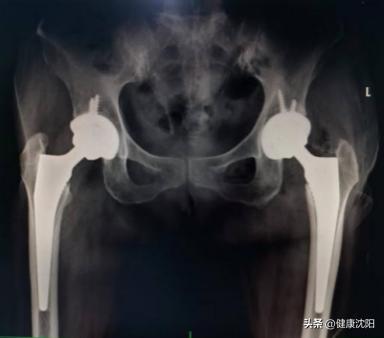

2.髋关节置换术。对于老年(年龄大于65岁)不稳定型股骨颈骨折、无法接受长期卧床休养、对再次手术耐受性较差或极高龄患者,推荐关节置换手术。

优点:早期恢复活动回归正常生活。

缺点:手术创伤相对较大,术后有人工关节脱位等风险。

对预期寿命长、术后功能要求高的推荐全髋关节置换术。对于活动要求低、身体情况欠佳的老年患者,肢体瘫痪者推荐人工股骨头置换术治疗。